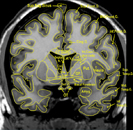

From the Brain Biodiversity Bank of Michigan State University, MRI sections through a living human brain as well as corresponding sections stained for cell bodies or for nerve fibers